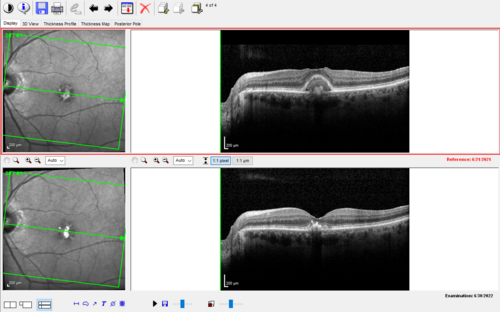

Pattern Dystrophy with Collapsed Vitelliform

74 year old female with vision loss in eye with collapsed vitelliform lesion.

Collapsed Vitelliform Pattern Dystrophy